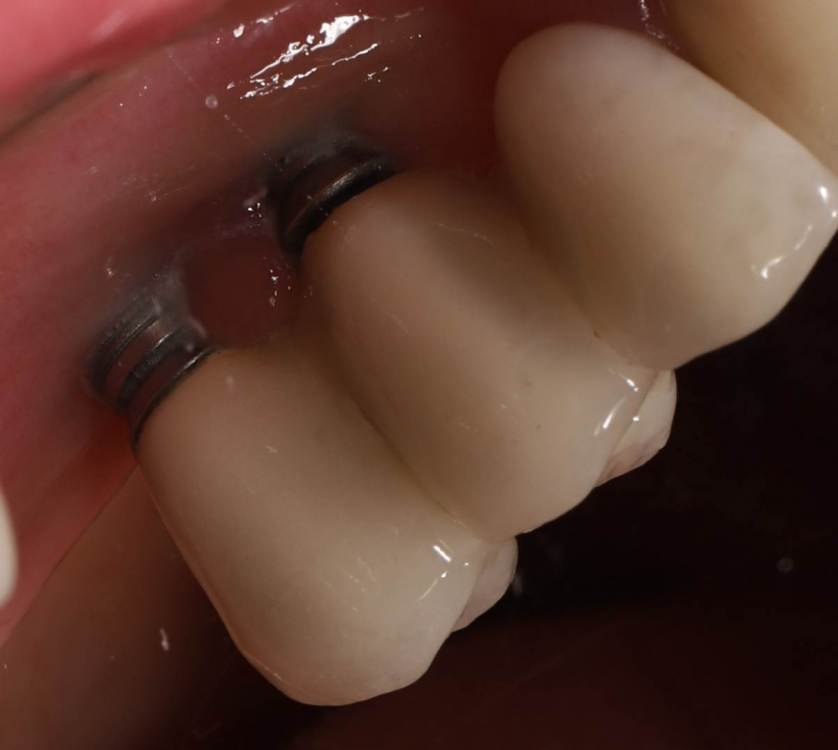

Ponchik Опубликовано 23 ноября, 2021 Поделиться Опубликовано 23 ноября, 2021 Заказ от начальства(ортопеда). Пациентка направлена ко мне со словами: вам сейчас косточки подсыпят, десенки пришьют и всё ок. Инересует второй сегмент, остальные и так ок. Работе всего пара лет. Делал не я. Импланты альфа-био. Прикреплёнки нет нигде. Всё хлюпает. Второй сегмент - я за удаление имплантов, через два месяца сунус+кость+мембрана(титан или полужесткая), через полгода 24, 26 импланты. Через 3 месяца мягкотканные дела, ещё через пару месяцев замаячит протезирование. (если всё остальное сложится) Как "подлепить" десну не снимая ортопедии, за два-три визита, хотя бы прикрыть витки? Я не знаю. Приму любой совет. Ссылка на комментарий

Ponchik Опубликовано 23 ноября, 2021 Автор Поделиться Опубликовано 23 ноября, 2021 1 минуту назад, АнтонТЛТ сказал: Витки заполировать Титановыми ёршиками? 2 минуты назад, АнтонТЛТ сказал: провести медикаментозную обработку Хлоргексидином или чем сильнее ? 2 минуты назад, Irouil сказал: А пациента что-то беспокоит? Только внешний вид Ссылка на комментарий

Ponchik Опубликовано 23 ноября, 2021 Автор Поделиться Опубликовано 23 ноября, 2021 Только что, АнтонТЛТ сказал: Фигня, он между витков не обрабатывает Пескоструй есть, буду им. Механическая и медикаментозная обработка это я представляю. Я с мягкими тканями не знаю что делать. И думаю A-oss (biooss жаба душит) какой добавить. Ссылка на комментарий

АнтонТЛТ Опубликовано 26 ноября, 2021 Поделиться Опубликовано 26 ноября, 2021 1 час назад, stommm сказал: Как вариант Только коронки не хотят снимать Ссылка на комментарий